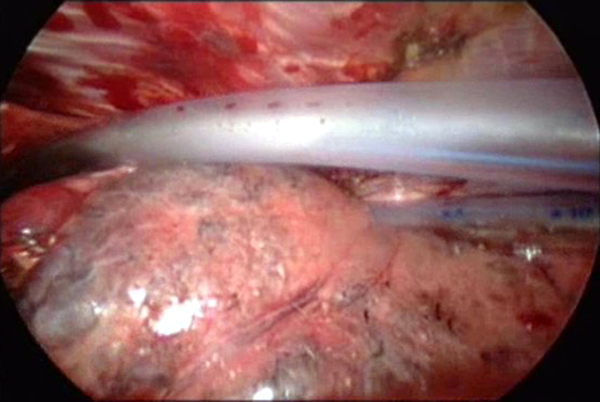

| Figure 3 |

Once the working incision has been made and the lung collapsed, further pressure on the upper lobe parenchyma with a tonsil sponge on a long curved ring clamp ensures complete collapse of the upper lobe. The mediastinal pleura around the upper pulmonary hilum is mobilized sharply or with cautery (Video 2). This allows for increased mobility of the upper lobe. A long curved ring clamp (Figure 3) introduced through the working incision is used to grasp the upper lobe at its apex and retract the lobe superiorly and laterally. This allows the surgeon to inspect the upper lobe and decide the position of the line of resection.